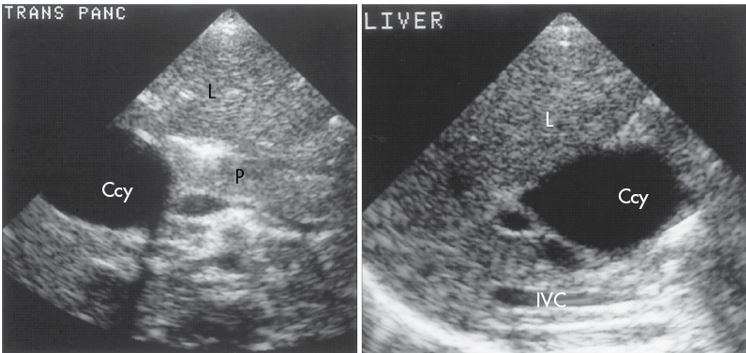

Transverse and longitudinal scan of a young patient with a choledochal cyst (Ccy) in the right upper quadrant.

Localized cystic dilation of the common bile duct

Diverticulum from the common bile duct

Invagination of the common bile duct into the duodenum

Dilation of the entire common bile duct and the common hepatic duct

4 pics of Choledochal Cysts